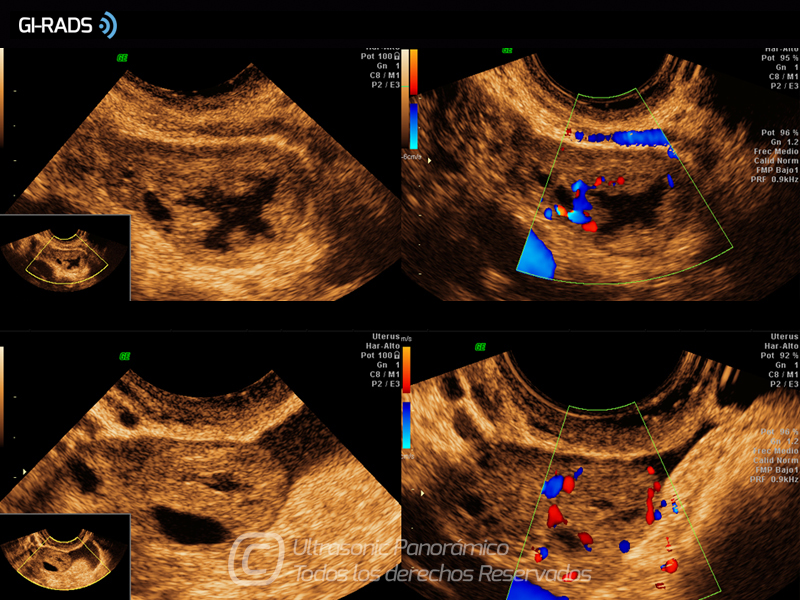

Imágenes Normales

• Imágenes Normales